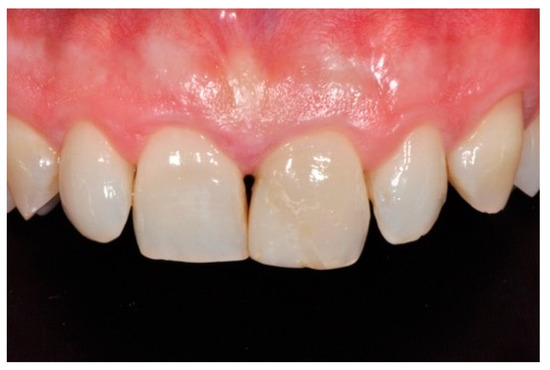

Figure 15.

Three months post-operative. Reprinted from Restauri diretti nei settori anteriori, G. Paolone, S. Scolavino, © 2021, with permission from Quintessence Publishing Italy.

Figure 16.

One year post-operative. Reprinted from Restauri diretti nei settori anteriori, G. Paolone, S. Scolavino, © 2021, with permission from Quintessence Publishing Italy.